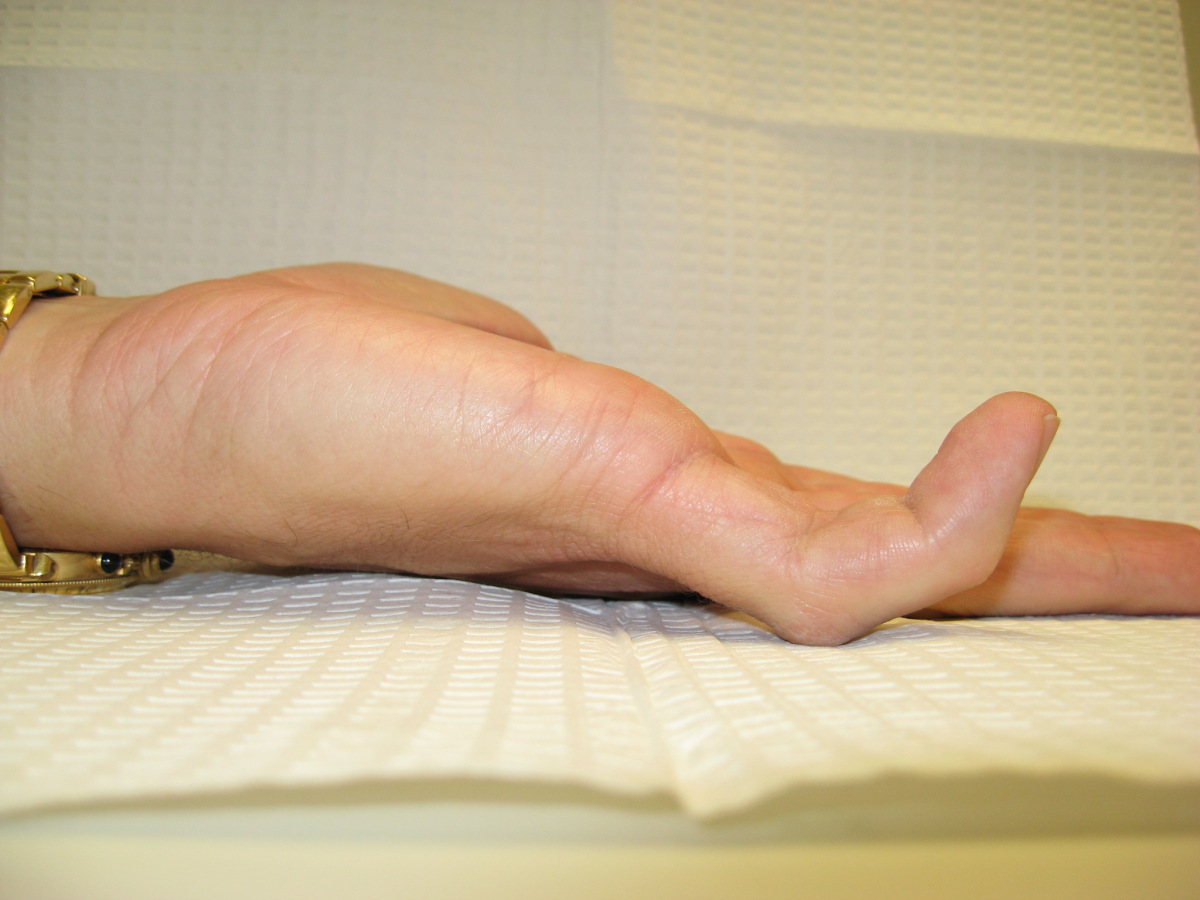

Case 5.

This 50 year old gentleman noticed Dupuytren disease of his left hand

five years ago. He now has bilateral contractures, worse on the right.